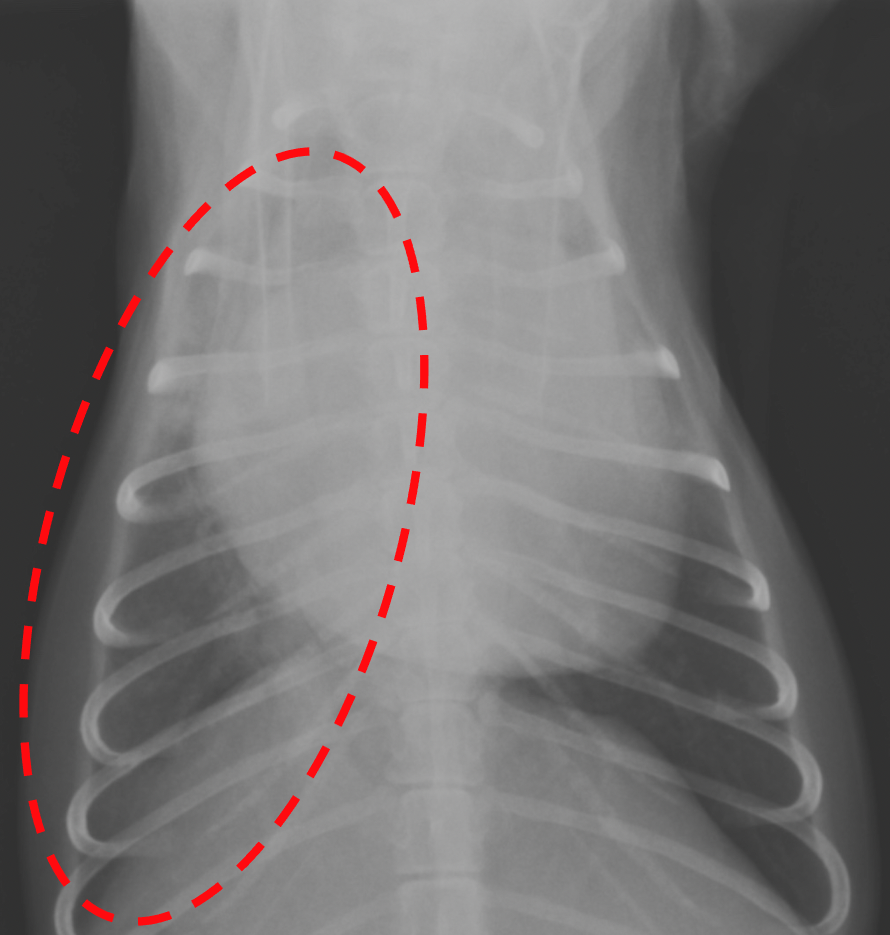

右肺の全域(点線)が白く、肺水腫が認められる。